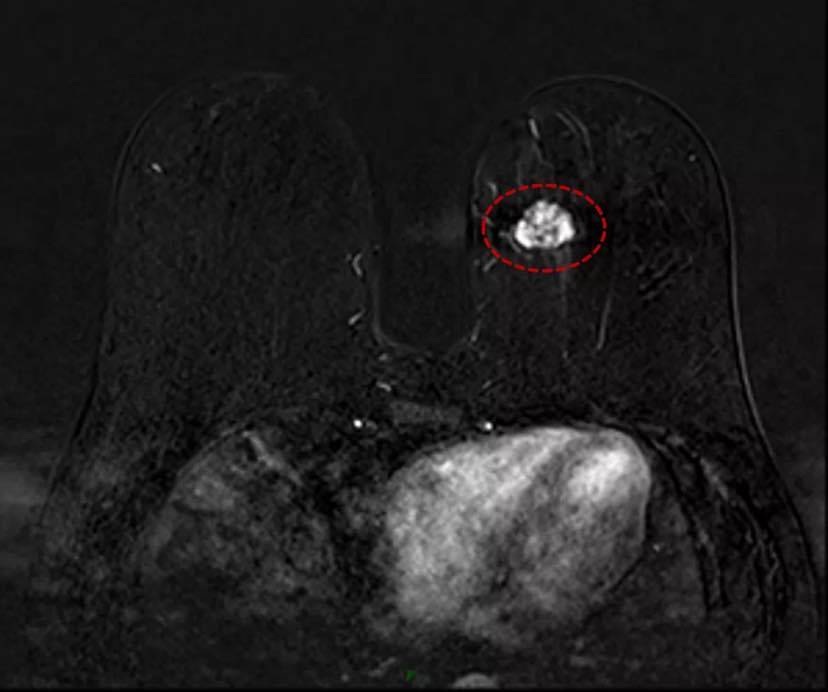

// 粘液癌在影像学上有什么特点?

粘液癌在B超上大多表现为低回声区;钼靶上表现为边界清楚的肿块或叶状肿块,可能与良性病变相似;在乳房磁共振T2加权像上显示高信号。

磁共振MRI:左乳内下象限见分叶状肿块,大小约23mm*20mm,边界不清,T1W1呈低信号,T2W1和压脂T2W1呈高信号。

粘液癌的磁共振成像